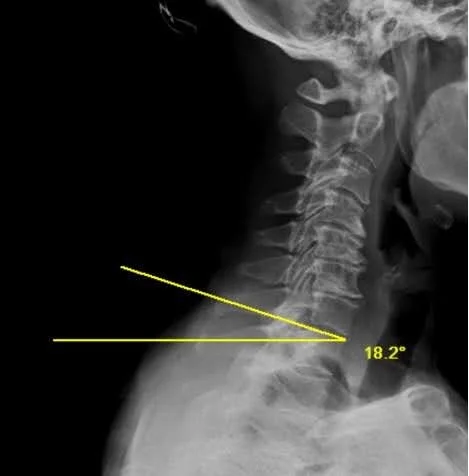

The T1 slope (T1S) is the angle between the superior endplate of the T1 vertebral body and the horizontal plane on a standing lateral radiograph. It serves as the foundational parameter for understanding cervical sagittal alignment, which many authors have suggested is similar to the role of pelvic incidence in the lumbar spine.

2) Instructions to Measure

•   Obtain a standing neutral lateral cervical spine X-ray with clear visualization of the T1 vertebral body; the patient should be in a comfortable upright position with horizontal gaze

•   Identify the superior endplate of T1 and draw a line along it

•   Draw a horizontal reference line (parallel to the ground)

•   Measure the angle between the superior endplate of T1 and the horizontal line; this is the T1 slope

•   A higher T1 slope indicates a more anteriorly tilted T1, which requires more cervical lordosis to maintain horizontal gaze; a lower T1 slope indicates a more horizontal T1 endplate with less lordosis required